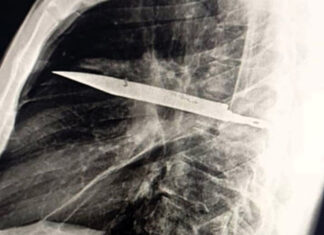

В Танзании мужчина прожил 8 лет с ножом в груди и...

В Танзании 44-летний мужчина прожил восемь лет с ножом в груди, не обращаясь за медицинской помощью....